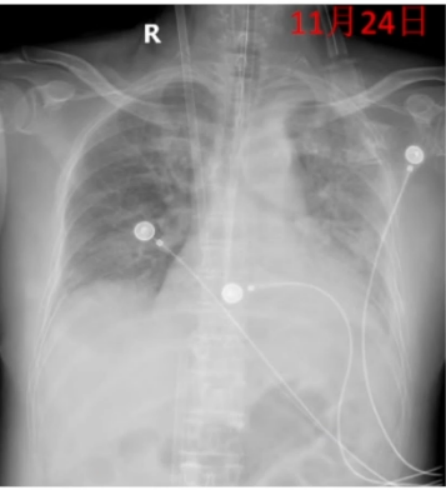

ECMO上机第9天,患者感染指标较前明显好转,ECMO参数及呼吸机参数均呈下调趋势,复查胸片较前好转(图8),氧合可,予VV-ECMO气流量调至0,逐步尝试撤机试验。

图片

8  复查胸片

10. ECMO撤机

11月24日上午7时启动撤机试验,持续至当天下午15时,期间维持氧浓度0.21,并将气流量调至0。监测显示,氧合指数未出现明显恶化,提示患者自身肺功能可在低辅助条件下维持氧合,遂实施ECMO撤离操作。

3  ECMO尝试撤机期间呼吸支持情况

11月24日15:40分成功撤离,共上机8天。

术后监护示:血压135/65 mmHg,心率93次/min,呼吸16次/min,SpO2 96%。

呼吸支持:PC模式,PC 17 cmH2O,f 18/minPEEP 7 cmH2O,FiO2 60%。

血气分析:pH 7.43,PaCO2 47.8 mmHg,PaO2 192 mmHg,HCO3- 31.5 mmol/L,氧合指数240 mmHg。